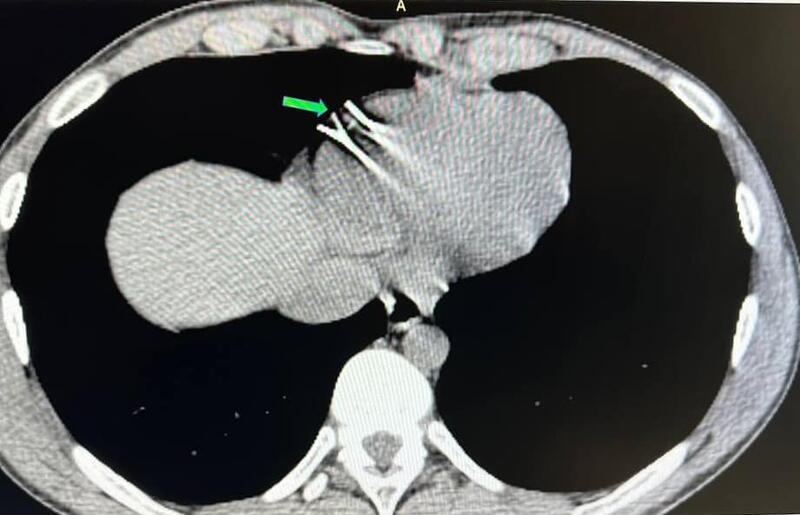

Молодий чоловік у віці 22 років отримав серйозну травму, яка включала ураження органів грудної клітки. Під час обстеження було виявлено два чужорідних предмети – металеві уламки, які проникли в стінку правого шлуночка серця.

Вінницька обласна клінічна лікарня імені М. І. Пирогова, у спеціальній гібридній операційній залі, успішно провела високотехнологічне хірургічне втручання на живому серці пацієнта без зупинки кровообігу. Операція виконувалась через міні-доступ – міні j-стернотомію, з використанням сучасних методів рентгеннавігації та магнітних пристроїв.